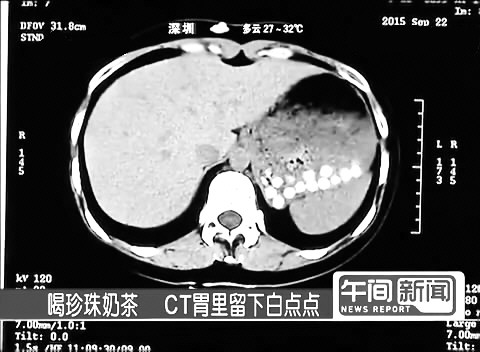

珍珠奶茶你还敢喝吗做CT胃里留下清晰白点

有媒体记者体验喝珍珠奶茶,照CT时在胃里发现清晰白点。医生推测,这说明这些“珍珠”里含有人体不能消化的物质,人吃了存在堵住肠胃甚至导致小肠梗阻的危险。

用手机扫描二维码,看看让这些医生都吃惊的白点吧。 (宗禾)